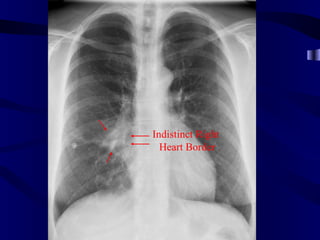

Indistinct Right Heart Border

Right Middle LobeAtelectasis